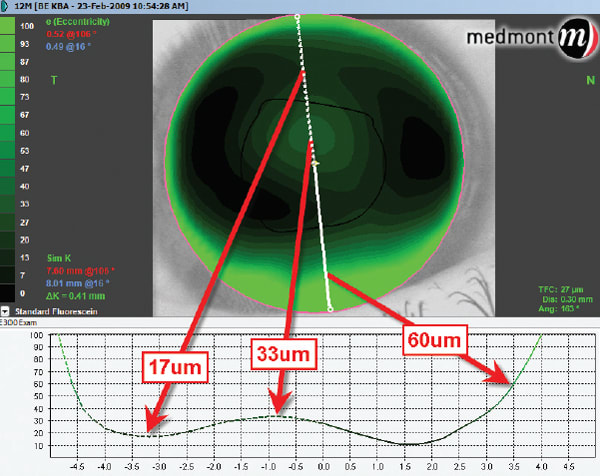

As an example, Figure 1 shows an image of the Medmont E300 contact lens module showing the theoretical fluorescein pattern of a keratoconus lens (KBA) on a patient who has oval keratoconus. The white line running vertically across the theoretical fluorescein pattern indicates the axis of the tear layer thickness on the graph below. Various tear layer thicknesses in microns are displayed along that axis line using arrows pointing to the same spot on the graph.

Figure 1: Image of the Medmont E300 contact lens module showing the theoretical fluorescein pattern of a keratoconus lens (KBA) on a patient who has oval keratoconus.